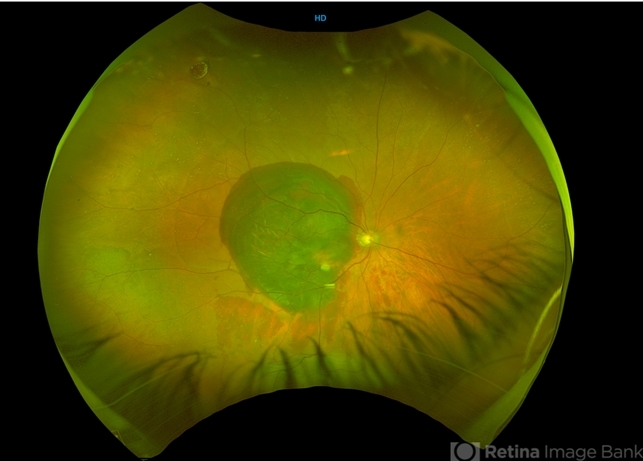

- subretinal blood, idiopathic polypoidal choroidal vasculopathy

- Dr. Anjana Mirajkar- HV desai eye hospital ,Pune

Fundus camera

optos - Description

- A widefield image of right eye of a 65 year old male showing large subretinal bleed at the posterior pole most likely in a case of PCV.